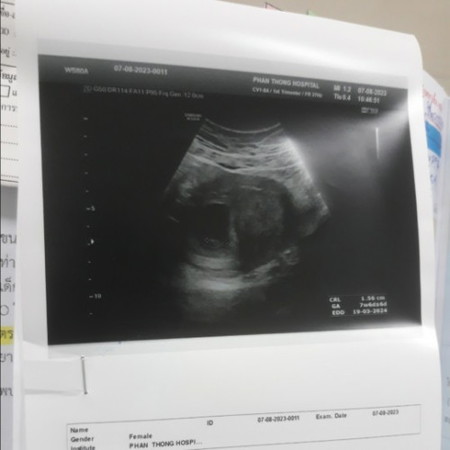

ไปฝากครรภ์ครั้งแรก

แม่ๆบ้านไหนไปซาวท้องตอน7สัปดาร์บ้างค่ะแล้วเจอคุณหมอกดที่ซาวท้องแรงบ้างค่ะ ตอนนี้เจ็บท้องมากกลัวลูกจะเป็นอะไร พอบอกหมอหมอก็ว่าไม่เป็นไรค่ะ ถ้ามีเลือดออกให้ไปที่โรงพยาบาลใหม่นะคะ ตอนนี้แม่เป็นกังวลมากเรยค่ะ#ขอบคุณล่วงหน้านะคะ #ขอบคุณสำหรับคำตอบค่ะ

บ้านนี้ฝากท้องครั้งแรกไปโรงพยาบาลหมอซาวได้6สัปดา3วันค่ะ หมอกดแรงค่ะเพราะหาตัวอ่อนไม่เจอน้องยังเล็กมาก โดนตรวจซาวช่องคลอดค่ะ ถึงจะเจอค่ะ